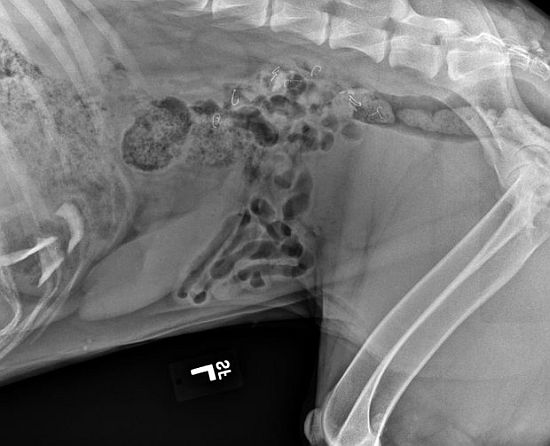

Carlson works at Washington State University and contacted a friend at the school’s College of Veterinary Medicine for advice. She was told she should bring the dog in for X-rays. The scans showed 15 flies had made it through the dog’s throat, stomach and intestines. The 16th fly was never found. (See X-ray below)

The X-ray with fly hooks clearly visible two-thirds up near the centre.